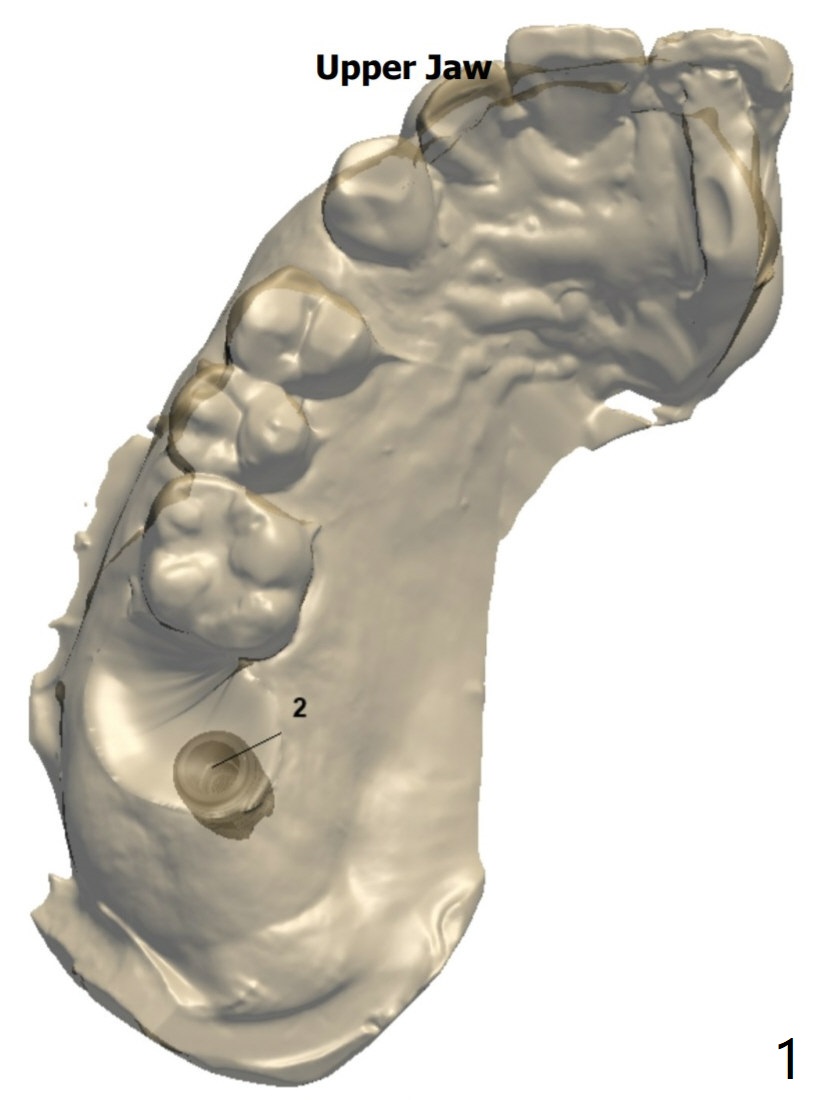

Implant Placed in Palatal Socket

Implant length changes to 10 mm. Place 5x9 mm IBS one. Use 4 and 4.5x10 mm IS dummy ones for sinus lift. Sinus Approach Kit and Treatment Planning one.